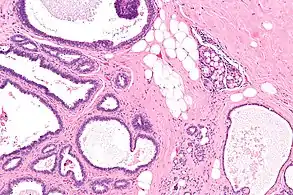

| Micrograph of collagenous spherulosis with the characteristic histomorphology - intratubular eosinophilic material with a spoke-like arrangement. H&E stain. | |

Collagenous spherulosis, or simple spherulosis, is a benign finding in breast pathology. It is almost always an incidental finding, though it is occasionally associated with calcifications, which may lead to a biopsy.

Collagenous spherulosis is characterized by a tubular/cribriform architecture with intratubular eosinophilic material that classically is arranged like the spokes of a wheel ("radial spikes"). There is usually no mitotic activity, and two cells populations (epithelial & myoepithelial) are present, like in benign breast glands.

The lesions are typically small (less than 50 spherules per lesion, less than 100 micrometers in size) and may be multifocal.